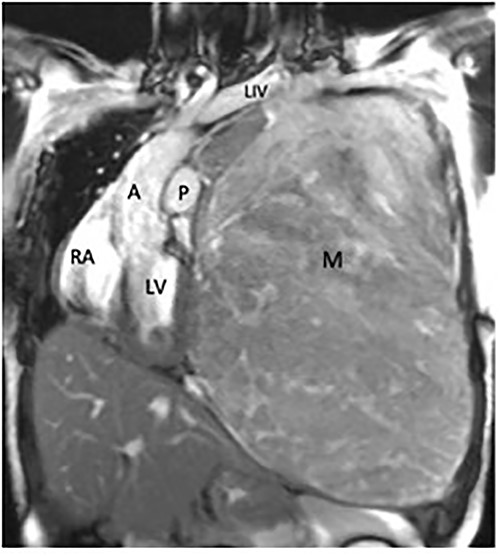

Coronal magnetic resonance image, showing the large heterogeneous mass occupying the left hemithorax. Note severe displacement of the heart and vasculature as well as complete atelectasis of the lung (L), left ventricle (LV), right atrium (RA), aorta (A), pulmonary trunk (P).